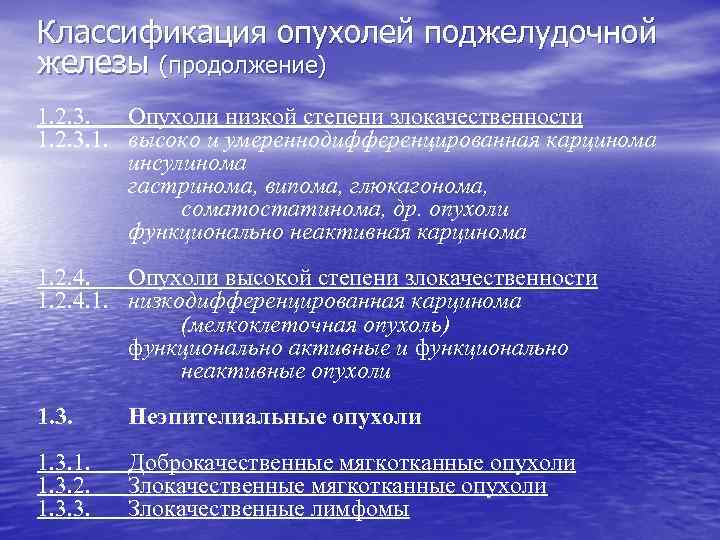

Классификация опухолей поджелудочной железы (продолжение) 1. 2. 3. Опухоли низкой степени злокачественности 1. 2. 3. 1. высоко и умереннодифференцированная карцинома инсулинома гастринома, випома, глюкагонома, соматостатинома, др. опухоли функционально неактивная карцинома 1. 2. 4. Опухоли высокой степени злокачественности 1. 2. 4. 1. низкодифференцированная карцинома (мелкоклеточная опухоль) функционально активные и функционально неактивные опухоли 1. 3. Неэпителиальные опухоли 1. 3. 1. 1. 3. 2. 1. 3. 3. Доброкачественные мягкотканные опухоли Злокачественные лимфомы